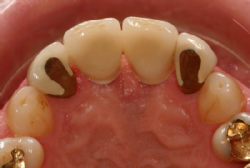

Abbildung 1: Ästhetisch unbefriedigende Situation nach Entfernung der oberen zentralen Schneidezähne